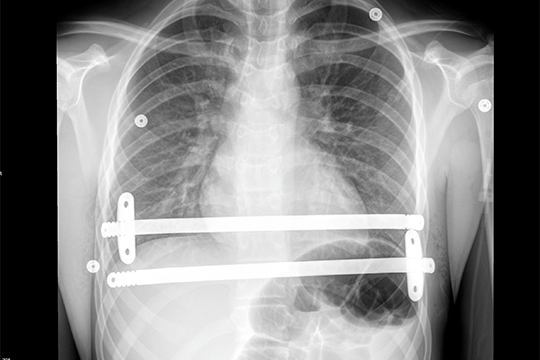

The X-ray results showed mounting pressure around Levi’s heart. He was diagnosed with a severe case of pectus excavatum.